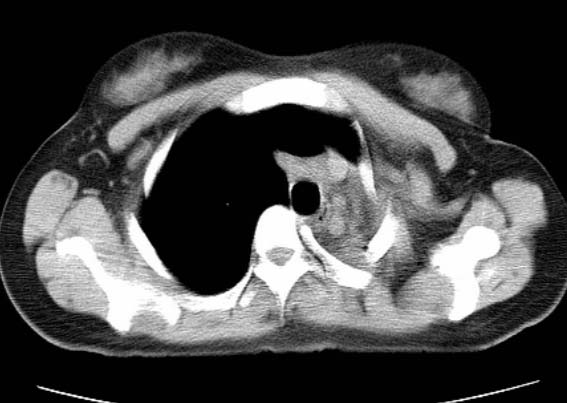

标题: CT25648:求教:是肺发育不全还是结核?

女  20岁。一月前咳血,诊“肺结核”抗痨治疗一月后,咳血停止,现复查。病人精神好。前后ct片对比未见明显变化。既往体检“正常”

1)考虑左肺结核并肺不张、支气管扩张。2)纵隔疝。

考虑左肺结核,左肺毁损,纵膈左偏,既往体检正常不可靠,tb一个月也不会这个样子的,有钙化,应该病程较长,冰冻三尺非一日之寒!

左肺发育不全。

考虑左肺结核,左肺毁损,纵膈左偏,既往体检正常不可靠,tb一个月也不会这个样子的,有钙化,应该病程较长,冰冻三尺非一日之寒

结核,左肺毁损。